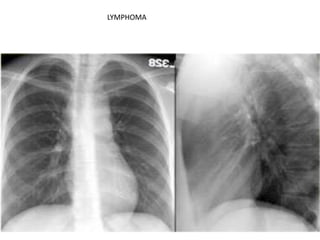

LYMPHOMA